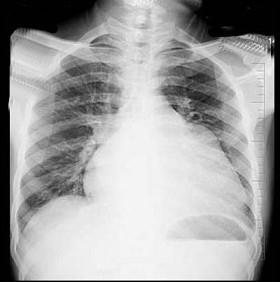

问题 56岁男性患者,劳累后心慌气促10余年,近来自觉症状加重。临床听诊,心尖区有舒张期隆隆样杂音,行胸部X检查,如图所示,你认为下列描述正确的是 ( )

选项 A、考虑三尖瓣狭窄 B、考虑二尖瓣狭窄 C、心后上缘后突压迫冲钡食管 D、左前斜位示心影向后下方突出 E、右前斜位示左心房增大

答案 BCDE